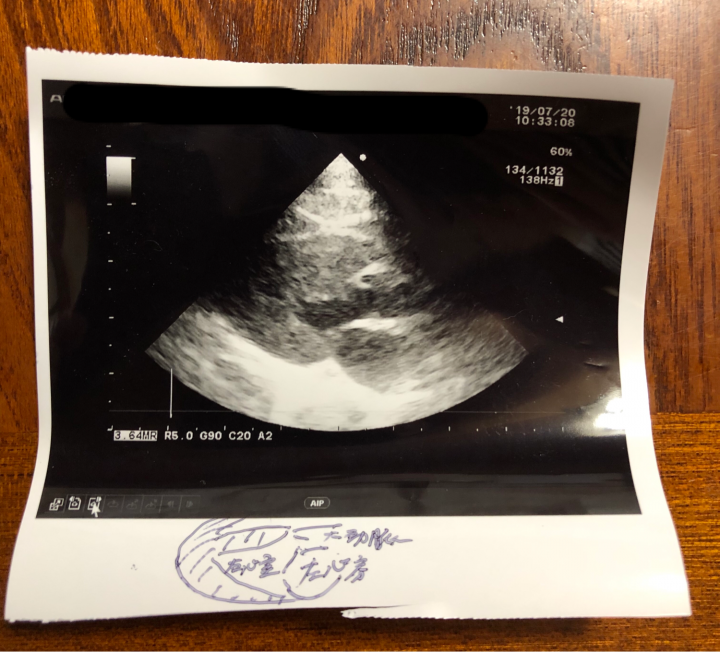

心筋の厚さも4ミリ(6ミリから肥大型心筋症)で正常。

大動脈と左心房が1:1.6

が正常でそれも大丈夫、

との事でした。

あと、初めてなんですが…

記念に

って獣医さんからエコーの写真もらいました。

記念にって…

どういう記念なんだろう🤔